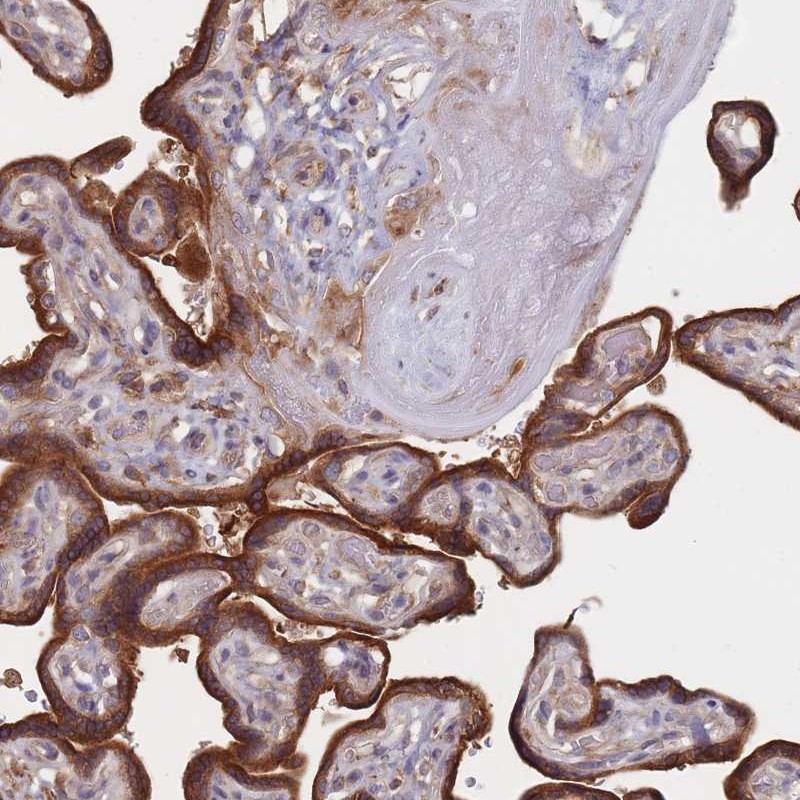

Immunohistochemical staining of human placenta shows strong cytoplasmic positivity in trophoblastic cells.